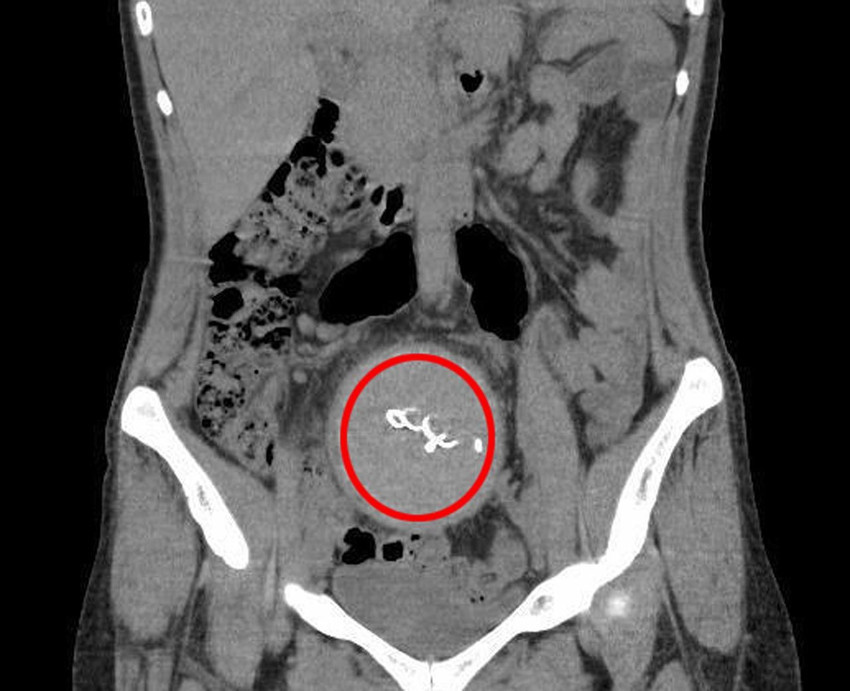

Antalya'da 2021 yılında özel bir hastanede doğum yapan Y.S.'nin vücudunda unutulan 30 santimetrelik gazlı bez, çekilen tomografi ile görüldü. Uzun süre ağrı çeken ve doğumda unutulduğu 2 yıl sonra ortaya çıkan gazlı bez, ameliyatla alınırken Sağlık Bakanlığı, kadının şikayetinden 2 yıl sonra sorumlular hakkında soruşturma izni verdi.

Antalya'da yaşayan Y.S., 2021 yılında kızını dünyaya getirmek için özel bir hastanede doğuma girdi. Burada sezaryen ile doğumu gerçekleştirilen Y.S., taburcu edildiği gün yaşadığı kusma ve ağrı şikayetiyle tekrar aynı hastaneye başvurdu. Bağırsaklarında yaşadığı sıkıntı nedeniyle 12 gün hastanede yatan Y.S., bebeğinden de ayrı kaldı. Annesinin emziremediği bebek, mama ile beslendi. Taburcu edilen Y.S.'nin bu kez de dikişlerinden iltihap akmaya başladı. Tekrar başvuran Y.S.'ye doğumunu yaptıran doktoru D.A., iddiaya göre; durumun normal olduğunu, iltihabın zamanla biteceğini söyledi. Hastaneden ayrılan Y.S.'nin 2 yıl boyunca ara ara ağrıları ve iltihap akıntısı devam etti. Bu süre zarfında başvurduğu hastanelerden sonuç alamayan kadın, ağrıyla geçen 2 yılın ardından 2023 yılında Antalya Eğitim ve Araştırma Hastanesi'ne başvurdu. Burada yapılan kontrolde, doktor acil tomografi çektirmesini istedi. 2023 yılının Ağustos ayında çekilen tomografide, Y.S.'nin vücudunda doğum sonrası unutulan sargı bezi görüldü. Şoke olan Y.S., 2 yıldır yaşadığı ağrılara ihmalin sebep olduğunu öğrendi. Y.S.'nin karnında unutulan yaklaşık 30 santimetre uzunluğundaki gazlı bez ameliyatla alındı. Y.S., hastane ve süreç içerisinde ihmali bulunan doktorlar hakkında savcılığa suç duyurusunda bulundu.

Çok zor günler yaşadığını belirten Y.S., 2 yıl boyunca ağrılarının ve ara ara iltihap akışının devam ettiğini söyledi. Y.S., "Farklı hastanelere de başvurdum ancak kimse teşhis koyamadı. En son Antalya Eğitim ve Araştırma Hastanesi'ne başvurdum. Burada bana doğum sırasında vücudumda sargı bezi kaldığı söylendi. Doğum yaptığımda 10 gün boyunca ağrılarım yüzünden çocuğumu kucağıma bile alamamıştım" diye konuştu. Suç duyurusunun ardından Sağlık Bakanlığı, olayla ilgili inceleme başlattı. İncelemede dosyada adı geçen sağlık personelinin ifadesine başvuruldu. Doktor D.A. ifadesinde; sorunsuz bir şekilde doğumun gerçekleştiğini, Y.S.'nin 2 gün sonra sağlıklı şekilde taburcu edildiğini, tıbbi kayıtlara göre ameliyathanedeki malzeme sayısının kayıtlara göre tam olduğunu söyledi. D.A. ifadesinin devamında, "Y.S.'ye yapılan ultrasonda yabancı bir cisim gözlenmedi. Gazlı bez tüm dikkatimize ve sayımımıza rağmen operasyon sırasında hastanın vücudunda kalmışsa steril olduğundan hastaya tıbbi bir zarar vermemiştir" dedi.

İfadesi alınanlar arasında yer alan ameliyathane hemşiresi Ö.Ö., pandemi sürecinde kendi hayatlarını hiçe sayarak anne ve bebeğin hayatını düşünerek hareket ettiklerini, ameliyat sonrasında malzemelerin tam olarak doktora bildirildiğini söyledi. Radyolojik görüntülemeyi yapan doktor E.B. ise doktor D.A.'nın talebi ile Y.S.'de yapılan görüntülemede; akciğer ve damarlara yönelik inceleme yaptığını, batındaki bir patolojinin görülmesinin imkansız olduğunu, incelemede bağırsakta genişleme ve sıvı gördüğünü söyledi. Doktor E.B. ifadesinin devamında şöyle dedi: "İnceleme alanıma girdiği kadarıyla batındaki bağırsak anslarında ileri derecede distansiyon (karın şişliği) olduğundan bahsedilmiştir. Yapılan ikinci gözlemde de bağırsaklarda geçiş tıkanıklığı tanısı konulmuştur. Benim gerçekleştirdiğim işlemde herhangi bir eksik ve atlama yoktur. Aksine Gossypiboma (hastanın vücudunda yabancı cisim unutulması) varlığında erken dönemde görülebilecek en olası patolojik durum olan tıkanıklık tanısı konulmuştur. Bundan sonrası klinisyenin değerlendirmesiyle sonuçlandırılabilecek bir süreçtir. Kullanılan gazlı bezin radyopak madde ile işaretli olmaması da tanısal gecikmede rol oynamıştır."